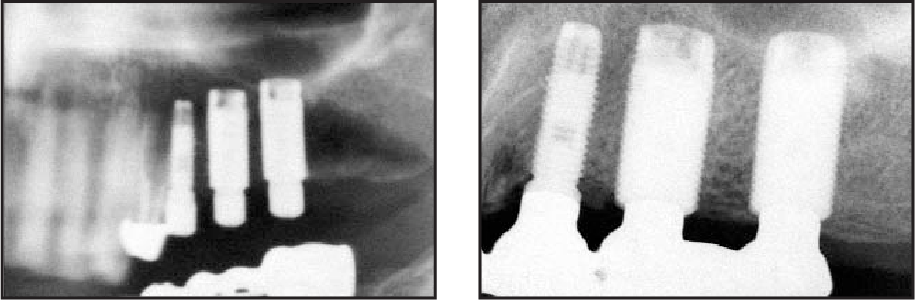

After a 5‑year period, the typical pattern of crestal bone resorption was not observed in Platform Switched implants.

The concept of platform switching is aimed at minimizing vertical bone loss by providing different diameters of the platform and the abutment.

a. Inward positioning of the implant‑abutment interface allowed the biologic width to be established horizontally, as an additional horizontal surface area is created for soft tissue attachment.

b. The PS design increases the distance between the inflammatory cell infiltrate at the micro gap and the crestal bone, thereby minimizing the effect of inflammation on marginal bone remodeling.

c. Reduction in stresses, especially in the crestal region, by shifting the stresses away from the bone-implant interface.